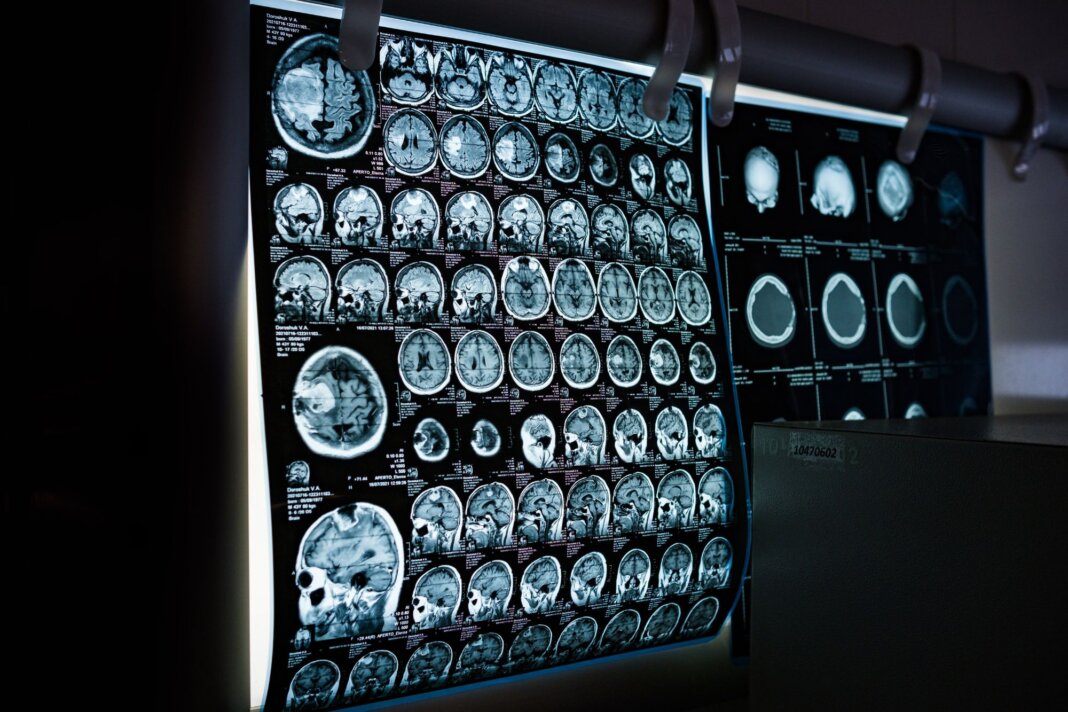

Cervello maschile e femminile: la differenza (sottile) è scritta nei geni

Donne e uomini sono davvero così diversi come siamo abituati a pensare? E bene, per secoli abbiamo alimentato il mito che i cervelli maschili e femminili fossero mondi alieni e incompatibili. Oggi, una ricerca pubblicata sulla rivista Science demolisce i cliché e ci consegna una realtà molto più sfumata e affascinante: non siamo pianeti diversi, ma lo spartito genetico dei nostri neuroni viene “suonato” con un volume leggermente differente a seconda del sesso biologico.

L’atlante da un milione di cellule

Lo studio, guidato da Alex R. DeCasien del National Institute of Mental Health, rappresenta una novità per le neuroscienze. I ricercatori hanno analizzato circa 1,2 milioni di cellule provenienti da sei diverse regioni della corteccia cerebrale di 30 donatori. Grazie a tecnologie di trascrittomica, la disciplina biologica che studia l’insieme completo degli Rna messaggeri presenti in una cellula, tessuto o organismo a singola cellula, il team ha potuto osservare l’attività di 680.000 neuroni eccitatori, 290.000 neuroni inibitori e centinaia di migliaia di cellule gliali, le instancabili “assistenti” del cervello.

Il risultato è una mappa ad altissima risoluzione che identifica dove e come i cromosomi sessuali e gli ormoni lasciano la loro impronta molecolare.